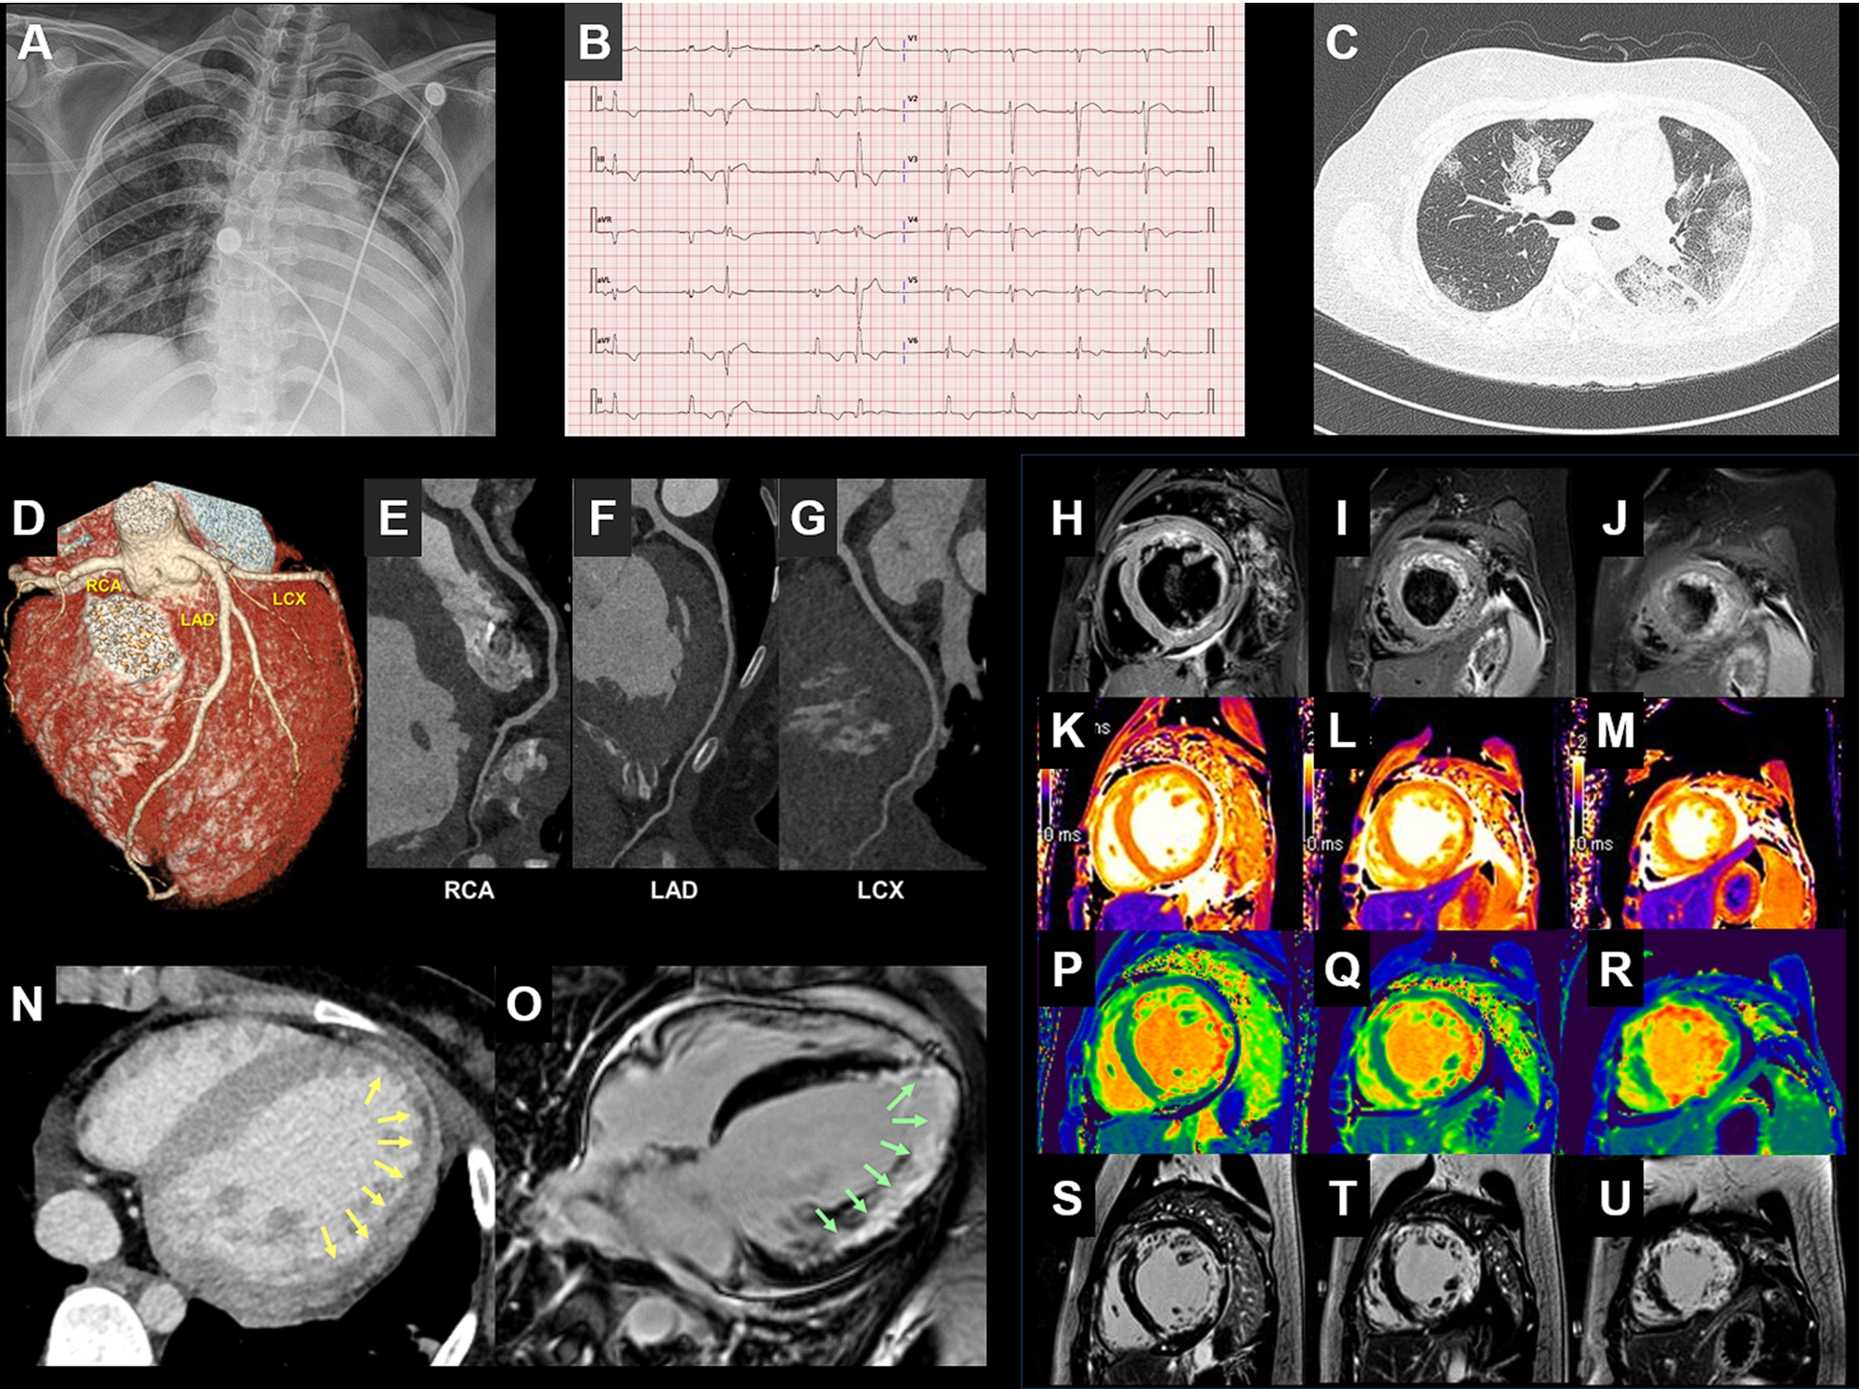

"코로나19가 심장질환 불렀다…21세 여성 국내 첫 사례보고"(종합)

COVID-19-related myocarditis in a 21-year-old female patient

https://academic.oup.com/eurheartj/article/doi/10.1093/eurheartj/ehaa288/5819437?searchresult=1

다른 장기와 더불어 심장 쪽 문제도 얘기가 나왔었습니다만, 국내 사례로는 처음이라고 하는군요.